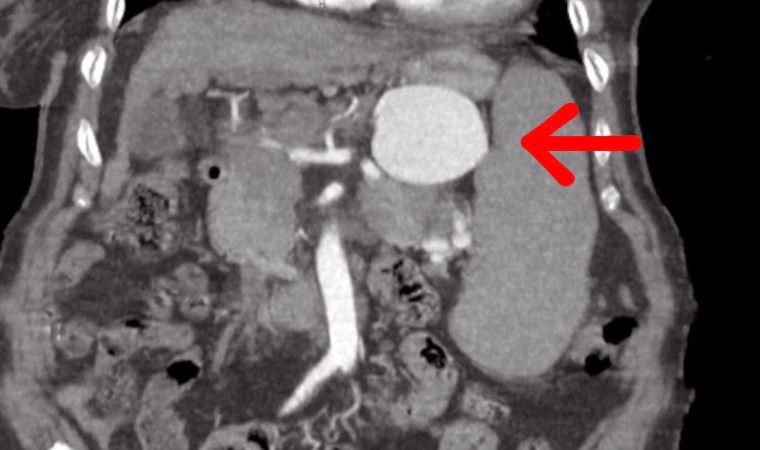

Yapılan ameliyat ile ilgili gazetecilere açıklamalarda bulunan Op. Dr. Volkan Burak Taban, hastanın gastroenteroloji kliniğinden kendilerine geldiğini, dalak arterinde ciddi bir anerizma şüphesinden bahsedildiğini söyledi. Değerlendirmeler sonrası ilaç tetkikleri istediklerini belirten Dr. Taban, "Yapılan tomografide teyzemizde dalak arterinde oldukça geniş dev diyebileceğimiz anerizmanın yani baloncuklaşmanın olduğunu gördük. Normalde dalak anerizması diyebilmemiz için baloncuklaşma diyebilmemiz için 20 milim yani 2 santimin üstüne çıkması lazım. Ama gördüğümüzde bizde şaşırdık. Çünkü yaklaşık 7 santimi geçen bir dalak anerizması vardı. Hastanın bu anerizmanın içerisinde tamamen kan dolduğu için her an patlama riski vardı. Allah korusun hastanın hayatını kaybetme riski ile de karşı karşıyaydık. Hasta ile ilgili hemen multidisipliner olarak bir değerlendirme yaptık. Hem gastroenteroloji, hem genel cerrahiden Serhat hocamız, hem radyoloji kliniğimiz ile beraber değerlendirme yaptık. Hastamızın 15 yıldır mücadele verdiği bir karaciğer sirozu da bizim kararlarımızda etkili oldu” dedi.